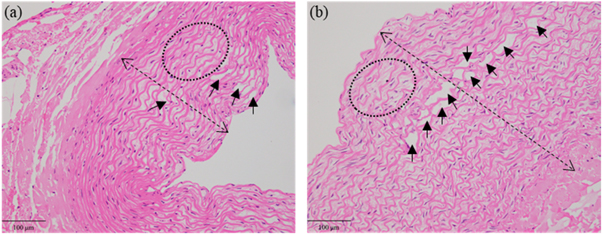

Figures 4(b) and (c) demonstrate that the microscope view of the post-sonication vessel was consistent with its histological section. In comparison with the vessel wall without sonication in figure 4(d), the sonicated vessel wall became thickened and multiple inward bulges (arrow heads) could be observed in figure 4(a). Besides, the elastic fibroblasts swelled with their intercellular spaces enlarged, and the cavities or microcapsules (arrows) appeared in some elastic fibroblasts. The elastic fibers degenerated in a wavy shape. Obvious hyalinization (stars) was found in the tunica adventitia.

Figure 4. H&E stains and microscope observation of one post-sonication vessel in group #7. (a) The pathological result of the treated area (200×). Cavities or microcapsules (arrows) between some elastic fibroblasts and multiple inward bulges (arrow heads). (b) The microscopic result of the whole vessel. (c) The pathological result of the whole vessel (20×). (d) The pathological result of the untreated area (200×).

Standard image High-resolution imageWith phantom #2 sonicated at 5.3 W, no cooling time was set and l was 4 mm. Figures 5(a) and (b) demonstrate the H&E stains of the vessel with 5 cm s−1 flow rate in group #7 and that without flow in group #9. After sonication, the vascular wall without flow was obviously thicker than that with 5 cm s−1 flow rate. The lumen area was decreased due to the thickened vessel wall. The number of cavities or microcapsules without flow was higher than that with 5 cm s−1 flow rate.

Figure 5. H&E stains of the vessels with 5 cm s−1 flow rate (a) and without flow (b). The double arrow indicates the wall thickness and the arrows indicate the cavities or microcapsules. The deformation of elastic fibers is shown in the ellipse.